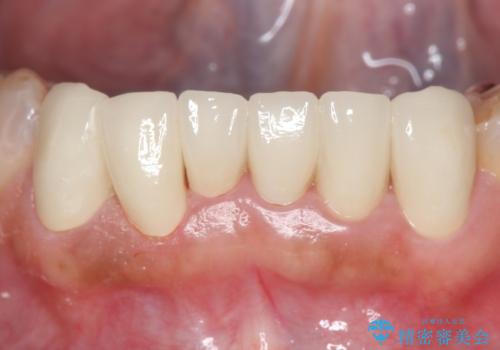

上顎は左側 4 番目から右側 4 番目までの 8 歯をオールセラミッククラウンで補綴しました。